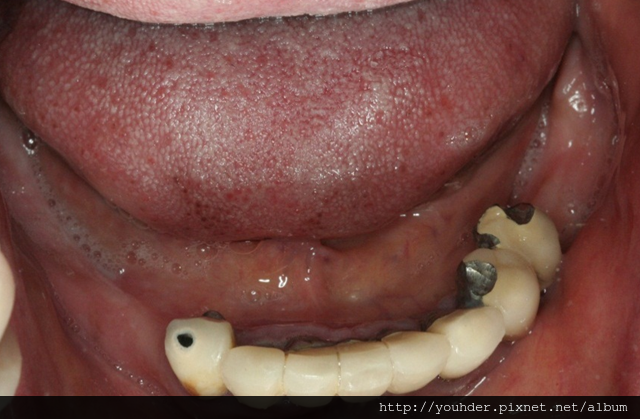

患者A先生

上顎 正面 下顎

患者B小姐

以上兩位患者口內狀況非常複雜,要制定一個好的治療計畫,

不只要考慮到患者的牙齒條件,

還要顧及患者意願、時間、金錢、評估可獲得的結果等等。

所以像這類型的Case 醫師通常在初步的溝通後會先做出一兩個不同的治療計畫,

再和患者解釋,了解患者接受程度。